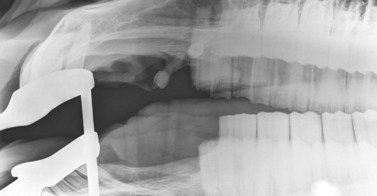

Lateral projection (Figs 13.513.7)

The lateral view is useful to visualize fluid lines and abnormalities of the maxillary or frontal bones or within the paranasal sinuses because the anatomy of the sinuses is not distorted by obliquity of the X-ray beam. The major disadvantage of the lateral view is that lesions cannot be localized to the left or right sides because both sides are superimposed. For this same reason, individual cheek teeth apices cannot be evaluated using this view.

The horse should be positioned with the lesion side adjacent to the cassette. The cassette should be held in the cassette holder in a vertical plane, parallel with the dorsal contour of the head, and as close to the head as possible. The primary beam should be horizontal and perpendicular to the long axis of the head. The primary beam should be collimated to reduce scatter, and rotating the light beam diaphragm unit to align it with the orientation of the horse’s skull helps to keep the collimation tight.

For maxillary cheek teeth, the beam should be centered just dorsal to the rostral aspect of the facial crest if the cheek teeth and/or paranasal sinuses are being examined. The entire facial area should be included to ensure that the entire maxillary cheek teeth row and all the paranasal sinuses are included in the radiograph. Hence, topographic markers for collimation include: the caudal aspect of the diastema (‘bars of mouth’) rostrally, the eye caudally, and the dorsal aspect of the skull (Fig. 13.6).

Lateral views of the mandibular cheek teeth are less frequently indicated, but the beam should be centered over the area of interest (usually indicated by a discharging tract or mandibular swelling), and rostrocaudal collimation should be adjusted to include the entire cheek teeth row, if possible. The thick masseter and pterygoideus muscles overlie the caudal three mandibular cheek teeth (Fig. 13.7), and hence higher exposures are required to image the apices of these teeth as compared to the rostral mandibular cheek teeth.

Fig. 13.7 Lateral radiograph of a normal mandibular cheek tooth row. Note that the soft tissue opacity of the thick masseter and pterygoideus muscles are superimposed over the caudal 3 cheek teeth.